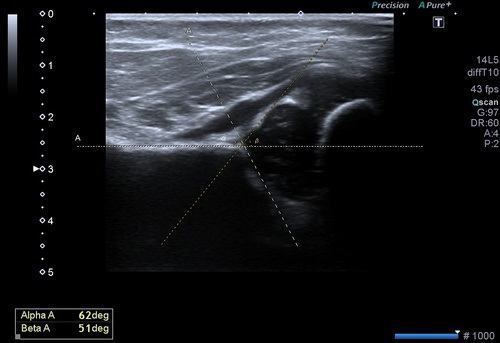

Bu inceleme de amaç her iki kalça eklemini oluşturan kemik yapıların, eklem ilişkilerinin ve kemik açılarının ölçülmesidir.

Bu ölçümler ile kalça gelişiminin normal olduğu, yavaş olup düzelme eğilimi olacağı ya da gelişim geriliği olduğu saptanır. Bu ölçümlerin optimizasyonu için uluslararası bir sınıflama sistemi kullanılır.